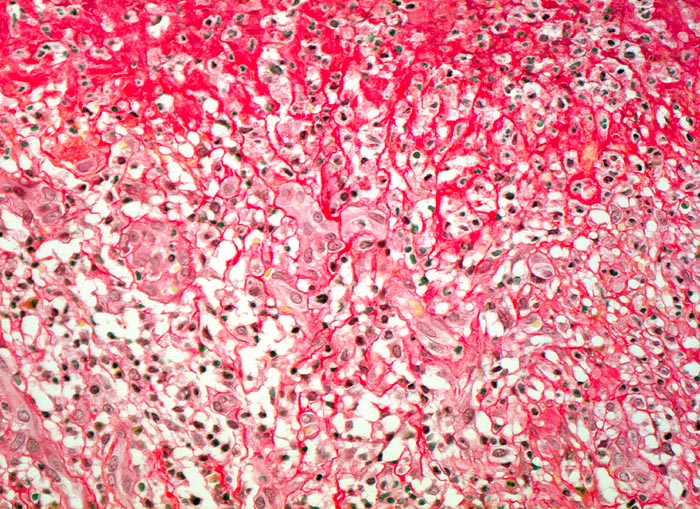

Das akute Ulkus ist rund, oval oder seltener polyzyklisch begrenzt und liegt meist im Schleimhautniveau. Das chronische Ulkus ist häufig kreisrund und im Längsschnitt trichter- oder treppenförmig. Die Schleimhautränder können lippenförmig über den Ulkusgrund hinausragen. Palpatorisch ist das chronische Ulkus aufgrund der narbigen Fibrose induriert. Die Schleimhautfalten laufen sternförmig auf das Ulkuszentrum zu. Das chronische Ulkus tritt zu 10%, das akute zu 25% multipel auf. Mikroskopisch zeigt das chronische Ulkus eine typische Schichtung (s. Bilder). Die Gefässe im Ulkusgrund zeigen eine starke Intimaproliferation mit teilweiser oder vollständiger Obliteration der Gefässlichtung. Morphologische Veränderungen in der übrigen Magenschleimhaut geben einen Hinweis auf die Ätiologie des Ulkus (Typ B oder C Gastritis).

• Schichtung: Detritus, oranges Quellungsfibrinoid, Granulationsgewebe, Narbe.

• Im Ulkusgrund arrodierte Arterie mit Intimafibrose und Abscheidungsthrombus.